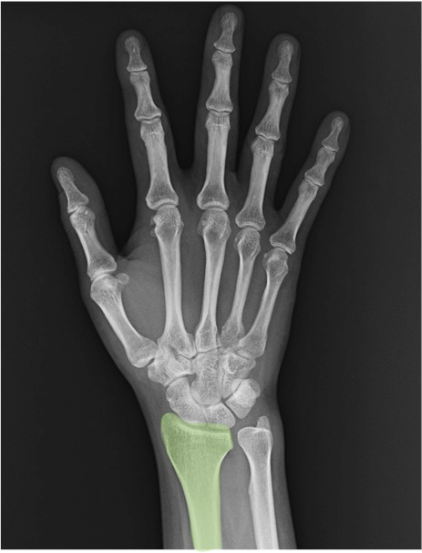

一目でわかる手根骨の解剖

手根骨、橈骨・尺骨、関節の解剖名とレントゲン画像所見

中手骨(metacarpal (bone))

第1〜第5の5本。PA像では基部(base)〜骨幹(shaft)〜骨頭(head)の連続性、骨皮質の途切れや骨梁配列をチェック。第1中手骨は短く、母指球側へ配列。

尺骨(ulna)

前腕の尺側骨。手関節X線では遠位部のみ視認。PAで橈尺関節(DRUJ)の整合、側面で重なり具合や背側/掌側転位の示唆を確認。

橈骨領域

橈骨(radius)

前腕の橈側骨。手関節X線では遠位橈骨(distal radius)が主要評価部位です。PA像では舟状骨窩(scaphoid fossa)と月状骨窩(lunate fossa)の連続性、DRUJ(遠位橈尺関節)の整合を確認。側面像では掌側傾斜(volar tilt)や背側転位、関節面段差(step-off)の有無をチェックします。